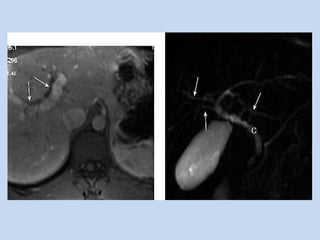

• In pancreatic carcinoma :

- depicts the ducts obstructed by the pancreatic

mass & localizes the obstruction to pancreas.

- “double duct sign” is observed in case of

pancreatic head mass. ( non- specific as it may

seen in chronic pancreatitis)

- MRA done in conjunction – assesses the

resectability..

APPLICATIONS • In pancreaticcarcinoma : - depicts the ducts obstructed by the pancreatic mass & localizes the obstruction to pancreas. - “double duct sign” is observed in case of pancreatic head mass. ( non- specific as it may seen in chronic pancreatitis) - MRA done in conjunction – assesses the resectability..